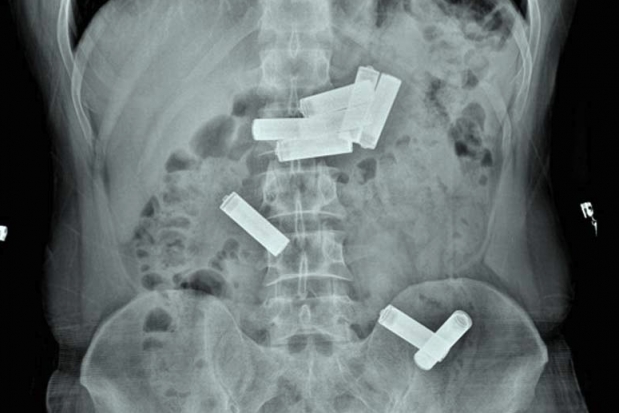

GAZİANTEP'te, işlediği bir suç nedeniyle hükümlü olarak cezaevinde kalan ve rahatsızlanınca hastaneye kaldırılan mahkumun midesinden 8 kalem pil çıktı.

Gaziantep Kapalı Cezaevi'nde kalan mahkum D.K., geçen hafta içerisinde koğuşunda rahatsızlanınca Dr. Ersin Devlet Hastanesi'ne götürüldü. Acil serviste muayenesi yapıldıktan sonra çekilen röntgende D.K.'nin midesinde 8 kalem pil olduğu saptanınca Endoskopi Servisi'ne sevk edildi. Gastroenteroloji uzmanı doktor Ahmet Yağbasan başkanlığındaki ekip, yaptığı çalışma ile D.K.'nin midesindeki pillerin birisini çıkardı. Uzmanlar, mahkumun midesindeki diğer 7 pilin müdahale yapılarak çıkarılmasının dokulara zarar vereceğini belirleyince takip altında doğal yollardan çıkarılması kararını verdi. Bunun üzerine servise yatırılan D.K., 2 gün sonra midesindeki pilleri doğal yollarla vücudundan çıkardı.

Tedavisinin ardından taburcu edilen mahkum yeniden cezaevine gönderilirken, doktor Ahmet Yağbasan karşılaştığı manzaranın kendilerini şaşırttığını söyledi. İğne, boncuk ve bozuk para yutan hastalarla sıkça karşılaştıklarını ancak ilk kez midesinde 8 kalem pil olan bir vaka gördüklerini anlatan Ahmet Yağbasan, şöyle dedi:

"Vaka bize cezaevinden karın ağrısı şikayetiyle getirildi. Acil serviste çekilen röntgende midesinde kalem pillerin olduğunu belirledik. Bunun üzerine hastayı endoskopi ünitesine aldık. Midede 8 pil olduğunu gördük ve bunları özel aletlerle çıkarmayı denedik. Yaptığımız müdahale ile birini çıkardık ama diğerlerinin pozisyonu uygun olmadığı için çıkaramadık. Pillerin içindeki kimyasal maddelerden dolayı doku hasarına yol açabileceğini kanaat getirerek, hastanın diğer 7 pili takip altında doğal yollardan çıkarmasını kararlaştırdık. Serviste yatan hastamız 2 gün sonra pilleri doğal yollardan çıkarmış oldu."

Doktor Ahmet Yağbasan, mahkumun psikolojik sorunları olmadığını intihar amaçlı olabileceğini düşündüklerini söylerken, pilin yutulmasının ardından 24 saat içerisinde acil servise getirilmemesi halinde hayati risk yaşayabileceğini de belirtti.